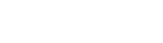

Echocardiography

Echocardiography